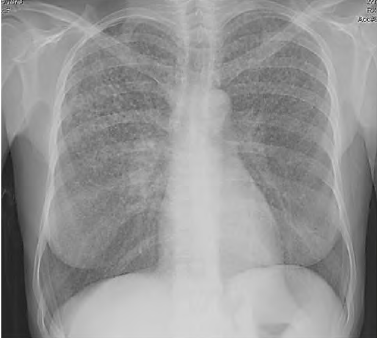

Uma paciente de 45 anos de idade compareceu, acompanhada pela filha, a uma consulta ambulatorial. Queixa-se de perda de peso (em torno de 4 kg nos últimos seis meses), febre vespertina e fadiga há mais de 20 dias. Observe que tem trabalhado muito, tem uma fadiga crônica e acha que iniciado os sintomas após exposição à chuva e o frio quando voltava do trabalho para casa. Ela informa que é etilista social e tabagista (15 cigarros / dia), e alguns exames laboratoriais como hemograma, eletrólitos, função hepática e renais normais. Os raios X de tórax estão representados na imagem a seguir. O resultado do PPD e o lavado brônquico são negativos.

Disponível em: <http://www.medicinanet.com.br/> . Acesso em: 12 nov.2020.

Com base nesse caso clínico, na imagem apresentada e nos conhecimentos médicos correlatos, julgue o item a seguir.

A febre vespertina, nesse caso, é patognomônica de tuberculose e fecha o diagnóstico do paciente mencionada.